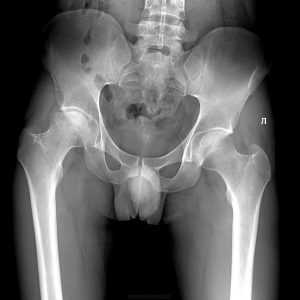

Рентген ТБС — диагностический метод исследования, который помогает выявить патологические изменения тазобедренного сустава, выполняющего ведущую роль в выполнении движений нижней конечности. Наиболее уязвимо сочленение в периоде новорождённости, так как выявляется множество аномалий развития и в возрастном периоде, на фоне остеопорозных изменений.

Рентгенограмма как метод исследования рассчитана на визуализацию костных структур. При диагностике хорошо просматриваются:

- Кости таза. Видны анатомические дефекты, переломы, трещины, асимметрия.

- Сустав. Выявляют вывихи, подвывихи, расширение суставной щели, сужение или сращение с формированием анкилозов.

- Головка бедренной кости. Просматривается вертел, шейка бедра, выявляются трещины, переломы, аномалии развития и строения, остеомиелитные и остеопорозные изменения.

Рентген тазобедренных суставов проводится как в раннем детском возрасте, так и более зрелом.

У детей рентгенограмма необходима при ограничении или асимметрии разведения ножек ребёнка в позе «лягушки» (малыш лежит на спине, ноги согнуты в коленях и разводятся в стороны), укорочение конечностей по отношению друг к другу, отсутствии упора на ножки у малыша.

Рентген тазобедренных суставов проводится в двух проекциях, которые помогают расширить визуализируемую анатомическую область и точно определить объем поражения:

- Передняя проекция. Пациента укладывают на спину, ноги разводят максимально в стороны, что позволяет раскрыть сустав и увеличить площадь диагностики.

- Боковая проекция. Пациент ложится на бок, вытягивает ноги вперёд.